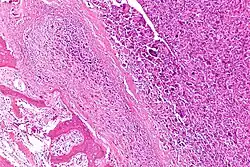

Intermediate-magnification micrograph of an osteosarcoma (center and right of image) adjacent to non-malignant bone (left-bottom of image): The top-right of the image has poorly differentiated tumor. Osteoid with a high density of malignant cells is seen between the non-malignant bone and poorly differentiated tumor (H&E stain). | |

Microscopically: The characteristic feature of osteosarcoma is presence of osteoid (bone formation) within the tumor. Tumor cells are very pleomorphic (anaplastic), some are giant, numerous atypical mitoses. These cells produce osteoid describing irregular trabeculae (amorphous, eosinophilic/pink) with or without central calcification (hematoxylinophilic/blue, granular)—tumor bone. Tumor cells are included in the osteoid matrix. Depending on the features of the tumor cells present (whether they resemble bone cells, cartilage cells, or fibroblast cells), the tumor can be subclassified. Osteosarcomas may exhibit multinucleated osteoclast-like giant cells.[22]